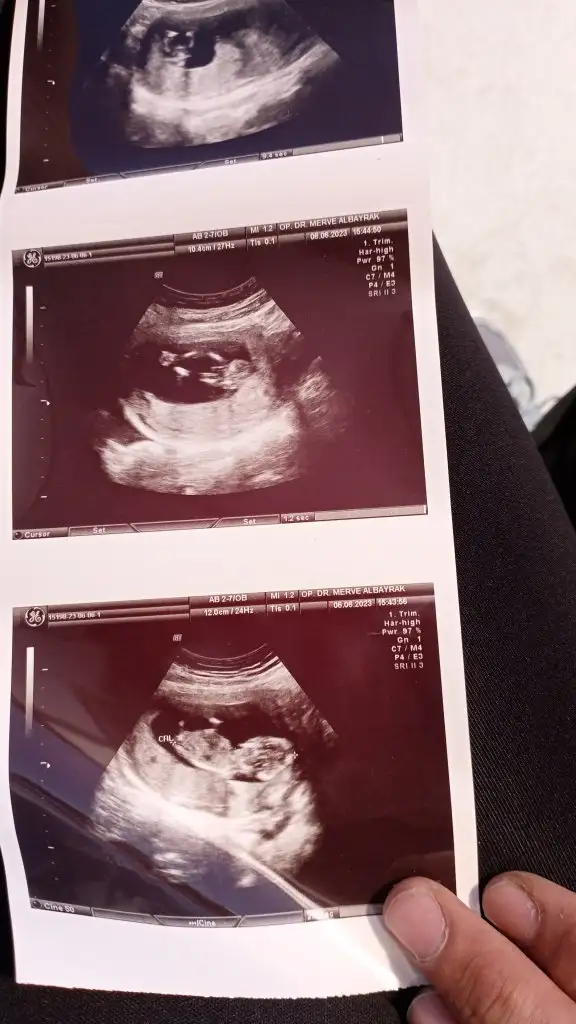

Meraba kızlar 13 haftalık ultrson resmi doktor mınık çıkıntı gördüğünü söyledi fakat çıkıntı üzüntü değil dedı gölge var dedı net ne kız nede net erkek dedı sadece erkek olabilir 1-2 hafta sonra net bellı olcak bırde siz balar mısınınz çok heyecanlıyım:) ıkılı test ıcın ense kalınlığna bakılınca orda çıkıntı yok kız dediler kafam çok karıstı

Valla bende esımde oğlum da kız hissediyoruz radyoloji uzmanı ense ölcüsü kız dedı çıkıntı sivri değil minik dedı erkek olsa 13 de sivri belirgin çıkıntı olur dedı bızım doktor emin olamadı sadece tahminde bulundu pazarteai gidicem inşallah net kız oldğu çıkar dedğinz gibi aay çok heyecanladnım:)